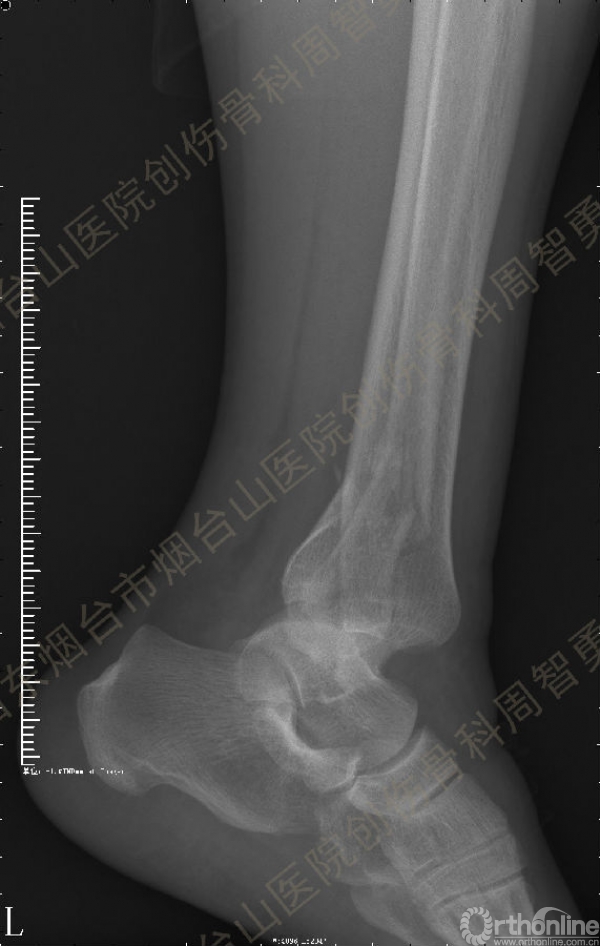

患者一般情况可,左踝关节肿胀,见皮下瘀斑,内、外、后侧有压痛,左踝关节主动运动受限,左足皮肤感觉、血供未见明显异常,左足趾各关节可主动运动。左踝关节正位X线片和CT重建示内踝内上方双层骨皮质影(图1a,c),CT示后侧骨折块分为后内侧骨折块和后外侧骨折块(图2a,b),后内侧骨折块累及内踝后丘,后丘骨折线呈冠状位(图2c),后内侧骨折块腹侧有向近端塌陷的小块骨软骨骨折块(图2d),CT也显示Chaput骨折块(图1c,2e)。

经典的后踝骨折发生于低能量旋转外力所致的踝关节骨折;标准pilon骨折见于高能量轴向暴力;而后侧pilon骨折是旋转外力和轴向暴力共同作用的结果,属于中等能量的损伤。踝关节骨折中的后踝骨折源自下胫腓后韧带的牵拉,骨折块位于后外侧,常为单一的三角形骨折块,大小从关节外片状骨折到累及胫骨远端关节面矢状径的40%(图4a)。后侧pilon骨折中的后侧骨折块较大,累及内踝后丘(三角韧带深层起点)在内的整个胫骨远端后侧,分为后内侧骨折块和后外侧骨折块,后内侧骨折块腹侧有向近端塌陷的骨软骨骨折块(图4b)。后侧pilon骨折中的内踝骨折线并不是水平位而是冠状位,可合并内踝前丘骨折。后侧pilon骨折踝关节正位X线片示特异性的内踝内上方双层骨皮质影(图1a,c)。这是由于后内侧骨折块的骨折线延伸到胫骨远端骨骺和干骺端的内侧骨皮质,其移位后的边缘成像所致。水平位CT显示后侧骨折块分为后内侧骨折块和后外侧骨折块,矢状位CT示后内侧骨折块腹侧有向近端塌陷的骨软骨骨折块。

↑图 1b

图 1 术前左踝关节正侧位X线片和CT重建,箭头所示内踝内上方双层骨皮质影(a,c)